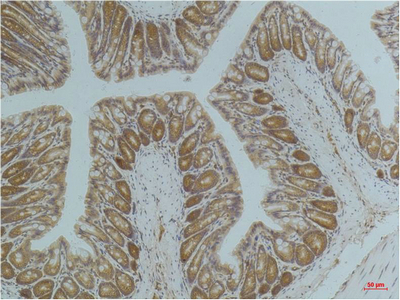

IHC-P analysis of mouse colontissue using GTX34141 AMPK alpha 1 antibody [5G11].

Dilution : 1:200